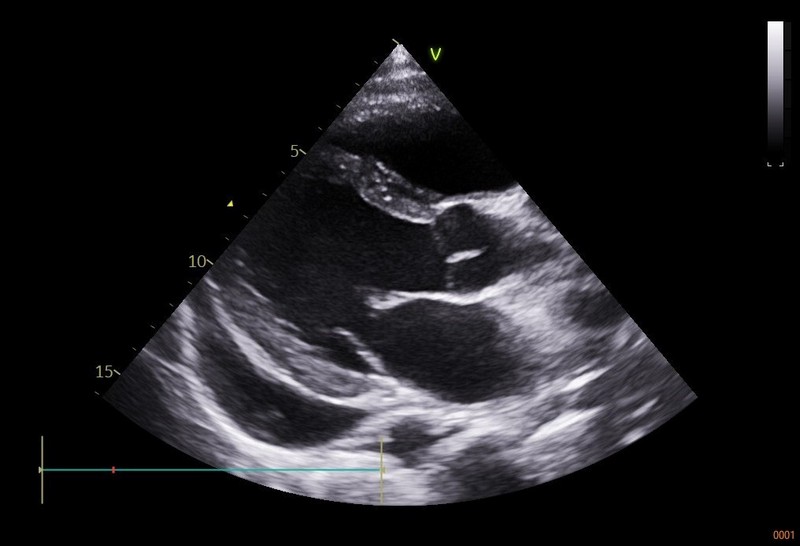

圖:心肌炎病患心臟收縮力下降,超音波檢查呈現心室擴大,同時合併心包膜發炎,所以也發現大量的心臟外積水,使得心臟舒張功能也受到影響。(王惠生提供)